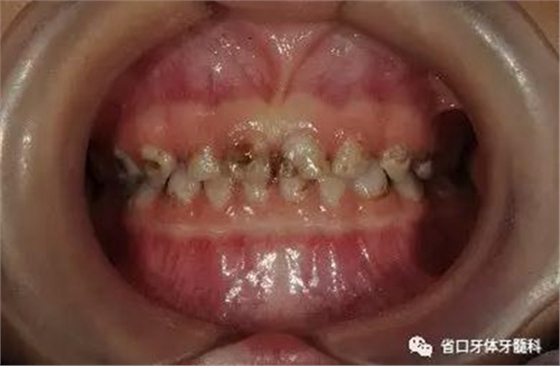

圖12 下前牙術(shù)前

圖14 術(shù)前